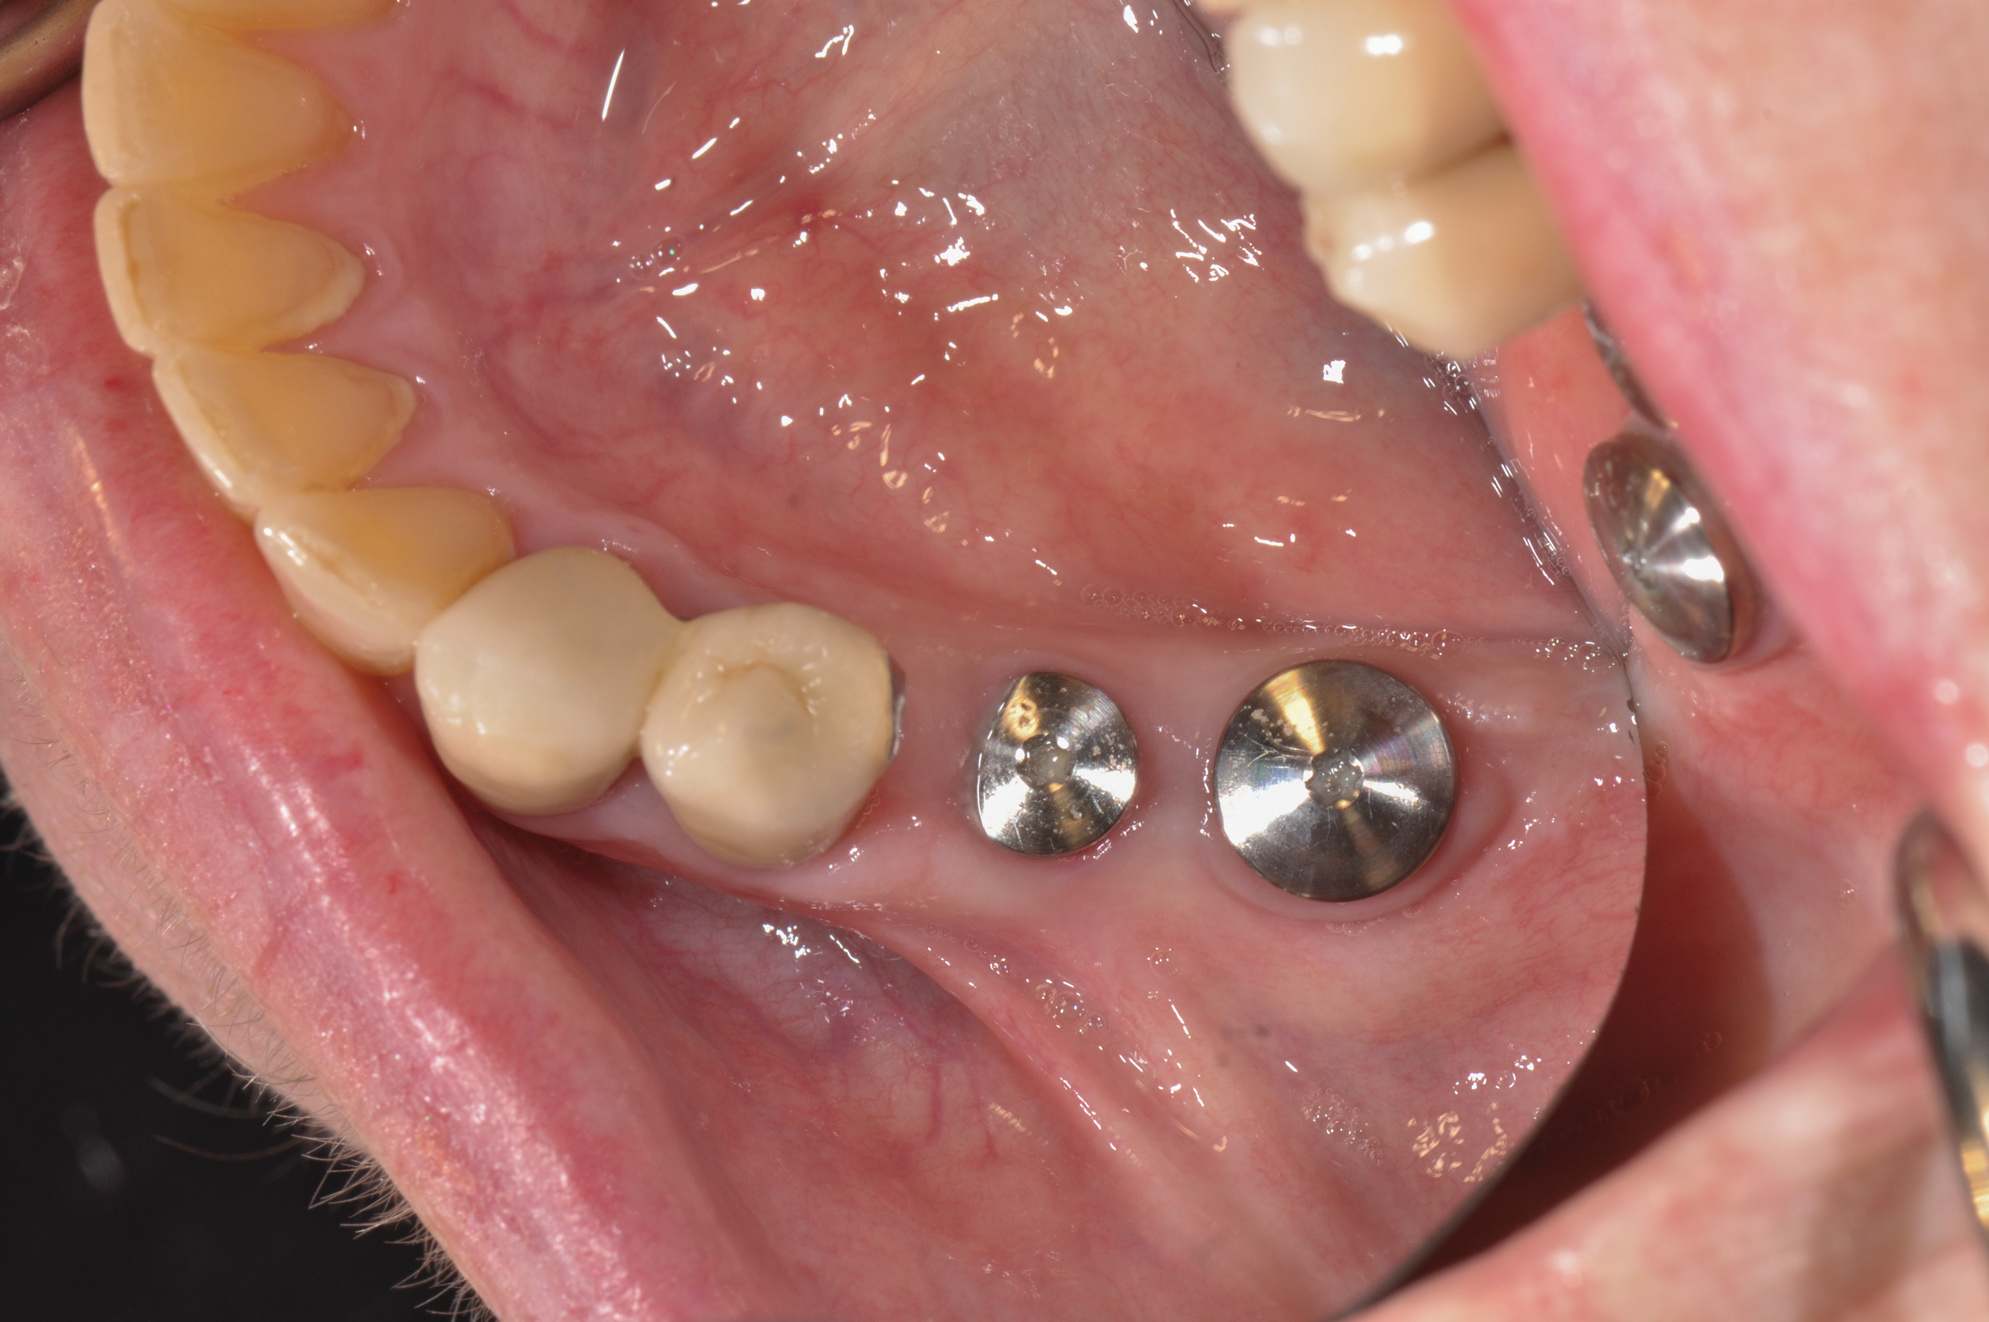

(3. THROUGH 5.) Poly (methyl methacrylate) (PMMA) bridge, custom healing abutment, and view of bridge bonded into place.

Figure 3

Figure 4

Figure 5